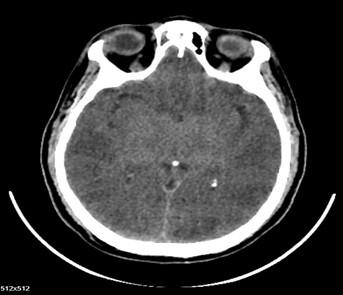

inued. Vasopressin gradually weaned off based on blood pressure. Serum ammonia levels were found to be elevated (140 µmol/L) and were managed with syrup Duphalac. A repeat CT brain performed on 24.02.2026 showed probable sequelae of hypoxic‑ischemic insult. In view of cerebral findings, anticoagulants were stopped and antiplatelets were withheld from 24.02.2026. Trial weaning from mechanical ventilation was attempted but was unsuccessful. The patient continued to require ventilatory support. Poor neurological prognosis was repeatedly explained to the attenders.

Fig (2): CT brain showed probable sequelae of hypoxic‑ischemic insult